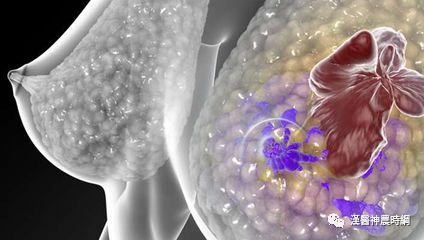

女性乳腺是由皮肤、纤维组织、乳腺腺体和脂肪组成的,乳腺癌是发生在乳腺腺上皮组织的恶性肿瘤。乳腺癌中99%发生在女性,男性仅占1%。

乳腺并不是维持人体生命活动的重要器官,原位乳腺癌并不致命;但由于乳腺癌细胞丧失了正常细胞的特性,细胞之间连接松散,容易脱落。癌细胞一旦脱落,游离的癌细胞可以随血液或淋巴液播散全身,形成转移,危及生命。目前乳腺癌已成为威胁女性身心健康的常见肿瘤。

乳腺癌引起皮肤改变可出现多种体征,最常见的是肿瘤侵犯了连接乳腺皮肤和深层胸肌筋膜的Cooper韧带,使其缩短并失去弹性,牵拉相应部位的皮肤,出现“酒窝征”,即乳腺皮肤出现一个小凹陷,像小酒窝一样。若癌细胞阻塞了淋巴管,则会出现“橘皮样改变”,即乳腺皮肤出现许多小点状凹陷,就像橘子皮一样。乳腺癌晚期,癌细胞沿淋巴管、腺管或纤维组织浸润到皮内并生长,在主癌灶周围的皮肤形成散在分布的质硬结节,即所谓“皮肤卫星结节”。